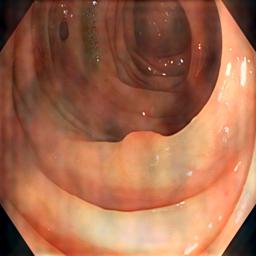

Polyp segmentation in medical imaging is crucial for the early detection and treatment of colorectal cancer [1, 2, 3, 4, 5, 6]. Accurate identification and delineation of polyps can significantly impact patient outcomes, but the task remains challenging due to variations in imaging conditions, equipment, and patient demographics. Traditional machine learning approaches for polyp segmentation often face difficulties when applied to data from different sources or domains, leading to reduced performance and generalization issues. Another difficulty is more common: constructing a large, diverse dataset is essential for robust and successful models, yet gathering such data in a centralized manner is often infeasible due to privacy laws and ethical concerns.

Table I presents our extensive experiments on the polyp segmentation results under FedAvg and FedProx frameworks and benchmarking results with other algorithms. For the metrics defined above, we have highlighted the best-obtained results in bold. Fig. 4 shows samples of the polyp segmentation results. Our comprehensive evaluations reveal that thresholding-based FDG methods (either soft or hard-thresholding) perform better than others.